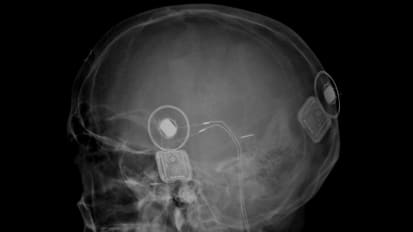

News Pushing the Envelope with Surgery to Restore Hearing: Notes from a Leading Otolaryngology Program